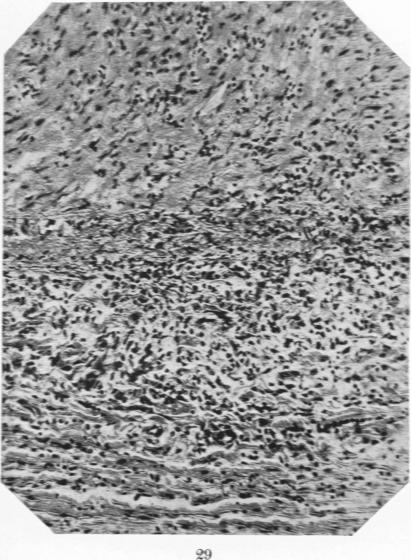

Studies in the Pathology of Rheumatic Fever: Two Cases Presenting unusual Cardiovascular Lesions.

Am J Pathol. 1927 Nov;3(6):583-594.19.